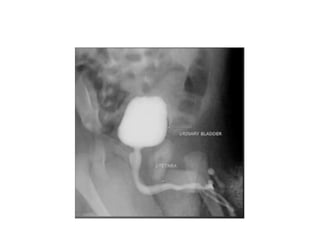

UIV

Chụp bể thận niệu quản

ngược dòng

• Mục đích:

- Đánh giá

hình thái và

các tổn thương

của thận- niệu

quản.

- Không đánh

giá chức năng

bài tiết của

thận

• Urographie	intraveineuse

Chụp	hệ	niệu	cản	quang	đường	tĩnh	mạch

-đánh	giá	tổng	quát	tình	trạng	hệ	niệu

-giải	phẫu

-chức	năng	hệ	niệu

Chỉ	định	UIV

• Tiểu	máu

• Sỏi	thận

• Bệnh	lý	nhiễm	trùng	hệ	niệu

• Bệnh	lý	u,	kén	thận

• Khảo	sát	chức	năng,	khảo	sát	bất	thường	hình

thái	hệ	niệu,	các	bệnh	lý	bẩm	sinh…

Tiến	hành

• Iode:	1-1,5	ml/kg,	TTM

• Các	phim:

-KUB

-Phim	sớm:ngay	sau	tiêm	thuốc,	đánh	giá	nhu	mô	và

đường	bờ	thận.

-Phim	5	phút:	đài	thận	và	bể	thận

-Phim	15	phút:	bể	thận	và	niệu	quản

-Phim	30	phút:	bàng	quang

(số	lượng	phim	và	thời	gian	chụp	tùy	thuộc	yêu	cầu	bệnh

lý	và	chức	năng	thận)